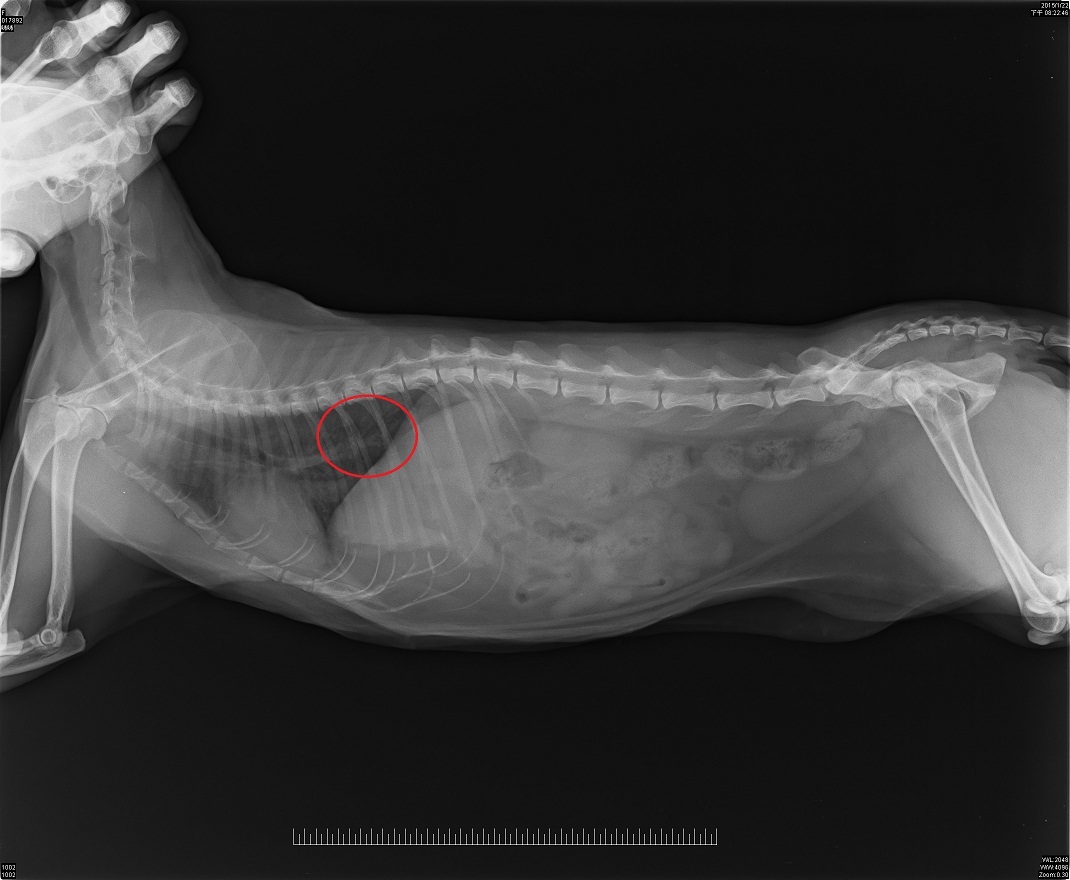

開刀傷口大但不會很深,可以不用住院上點滴,但這幾天須回院打針消炎檢查傷口。照X光亦發現肺部有2個小小的白色圓點,目前研判尚未有擴散的跡象,毋須化療,但要定期追蹤肺部的小白點。

Doraemi於2/7拆線,傷口下半部分也癒合的很完整,觸診身體其他部分也無特殊異狀,原本肺部的小陰影約3月初再照X光追蹤檢查。動物近況說明: 目前DORAEMI在志工家休養,身型越來越圓潤,毛色也亮麗許多,希望MI能健康久久,謝謝大家的捐款,萬分感謝